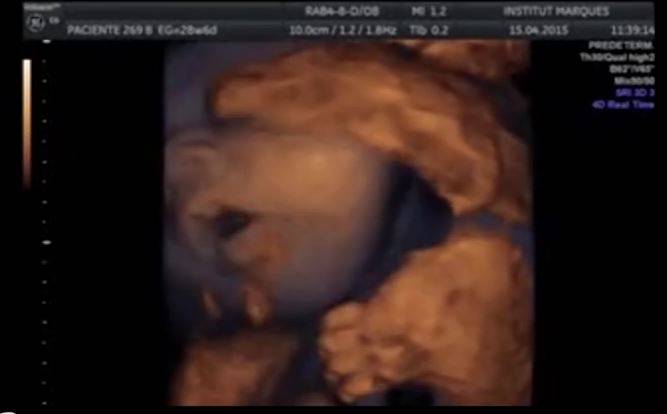

(Screenshot video Institut Marquès)

L’altro esperimento è stato quello di far ascoltare la musica ai feti per via addominale. Sulla pancia della mamma sono state posizionate delle cuffie ad un volume di 98,6 decibel. Anche in questo caso, tuttavia, come in quello di parlare al pancione, non sono stati osservati cambiamenti nei movimenti o nelle espressioni dei feti. Niente linguaccia, insomma.

Con questi risultati i ricercatori hanno “dimostrato che i feti possono sentire dalla settimana 16, quando misurano 11 centimetri, solo se il suono proviene direttamente dalla vagina. Pertano, “i feti riescono a malapena a sentire il rumore che proviene dall’esterno. Quindi, possiamo dire che il mito di parlare alla pancia delle donne incinte è storia passata”, così Marisa Lopez-Teijón, autrice principale dello studio dell’Isntitut Marquès, già premiata in passato presso l’Università di Harvard con l’Ig Nobel per la medicina nel campo dell’ostetricia per la scoperta dell’udito fetale.